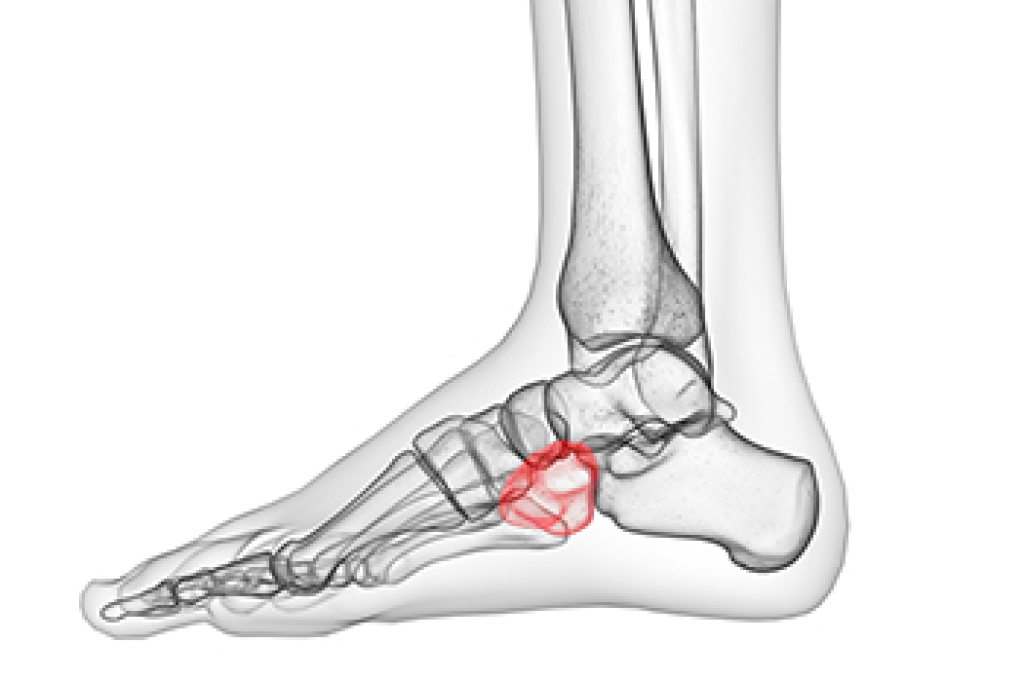

Cuboid syndrome occurs when the cuboid bone in the midfoot becomes partially dislocated (subluxes). This can occur during an acute injury such as an inversion sprain of the ankle, or over time from jumping, running, etc., which can place repetitive strain on the muscle which attaches to the lateral (outer) side of the foot. When the cuboid bone subluxes, this can prevent surrounding bones from moving properly. It is believed that having flat feet, or a gait where your foot rolls inward when you walk may put you at higher risk of developing cuboid syndrome. Symptoms of cuboid syndrome can include lateral foot pain which worsens in the morning or during activity, swelling and tenderness in the area, an overall feeling of weakness or difficulty when walking, running or jumping. If you believe you may have cuboid syndrome, make an appointment with a podiatrist as soon as possible. They will use a variety of imaging and physical tests to assess your condition and create a comprehensive treatment plan to guide the cuboid bone back into position and relieve pain and swelling.

Cuboid syndrome is a common cause of lateral foot pain, which is pain on the outside of the foot. The condition may happen suddenly due to an ankle sprain, or it may develop slowly overtime from repetitive tension through the bone and surrounding structures.

Diagnosis of cuboid syndrome is often difficult, and it is often misdiagnosed. X-rays, MRIs and CT scans often fail to properly show the cuboid subluxation. Although there isn’t a specific test used to diagnose cuboid syndrome, your podiatrist will usually check if pain is felt while pressing firmly on the cuboid bone of your foot.